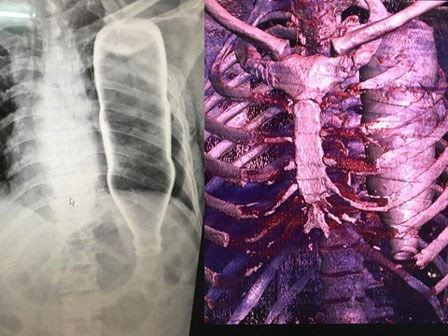

Ho ra máu, tá hoả phát hiện khối u "khủng": BS khuyến cáo những dấu hiệu cần đi khám sớm

Nam sinh viên 23 tuổi với các biểu hiện đau ngực, khó thở rồi bỗng xuất hiện ho ra máu bàng hoàng khi bác sĩ thông báo có khối u tế bào mầm kích cỡ khủng ở trong lồng ngực.